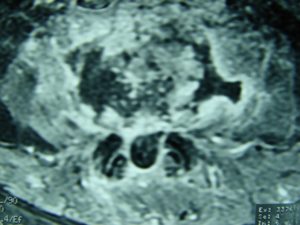

Μαγνητική Τομογραφία της Ο.Μ.Σ.Σ. (13/06/2007) Ακολουθία Τ1 και Τ2

Οβελιαία τομή (α,β) Παρατηρείται η ύπαρξη Επισκληριδίου Αποστήματος στο επίπεδο Ο3-Ο4 που προκαλεί μεγάλη στένωση του σπονδυλικού σωλήνα, με απώθηση του νωτιαίου σάκου. Διαπιστώνεται επίσης η ύπαρξη παρα-σπονδυλικού αποστήματος

Εγκαρσία τομή (γ,δ) Παρατηρείται η ύπαρξη Επισκληριδίου όπως επίσης και προ-παρασπονδυλικού αποστήματος.